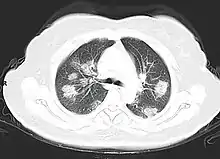

Imaging

Chest CT scans may be helpful to diagnose COVID‑19 in individuals with a high clinical suspicion of infection but are not recommended for routine screening.[160][172] Bilateral multilobar ground-glass opacities with a peripheral, asymmetric, and posterior distribution are common in early infection.[160][173] Subpleural dominance, crazy paving (lobular septal thickening with variable alveolar filling), and consolidation may appear as the disease progresses.[160][174] Characteristic imaging features on chest radiographs and computed tomography (CT) of people who are symptomatic include asymmetric peripheral ground-glass opacities without pleural effusions.[175]

Many groups have created COVID‑19 datasets that include imagery such as the Italian Radiological Society which has compiled an international online database of imaging findings for confirmed cases.[176] Due to overlap with other infections such as adenovirus, imaging without confirmation by rRT-PCR is of limited specificity in identifying COVID‑19.[175] A large study in China compared chest CT results to PCR and demonstrated that though imaging is less specific for the infection, it is faster and more sensitive.[159]